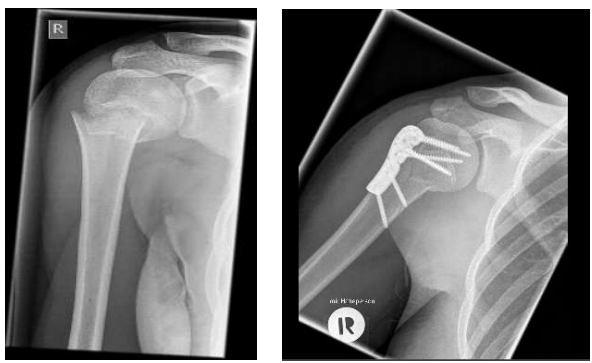

Schulterluxation

Abschlagen, Eindellen des Knochen → Hill-Sachs-Läsion

Schultergelenkluxation

a) Nach unten

b) Nach vorn

c) Nach hinten

d) Sonderform

c & d sind selten

Schulter zügig einrencken

verschiedene Arten der einrenckung

normalerweise kurze Einsätze der Rettungskräfte

Vorsicht ist wichtig → kann sich um andere Luxation handeln

Oberarmbruch - Subcapital

Nagel soll Position fixieren und Knochen zum heilen bringen

mit vielen, zielgerichteten Schrauben Knochen an richtigen Platz bringen